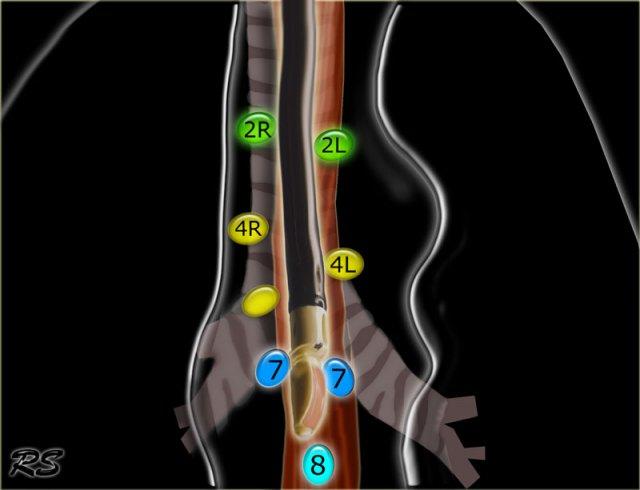

Bản đồ hạch bạch huyết IASLC 2009

Phân loại hạch bạch huyết vùng trong phân giai đoạn ung thư phổi, được điều chỉnh từ sơ đồ phân vùng của Hội Lồng ngực Hoa Kỳ

2R.Cạnh khí quản trên

Hạch nhóm 2R trải dài đến bờ bên trái của khí quản.

Từ bờ trên của cán ức đến điểm giao nhau giữa bờ dưới tĩnh mạch vô danh (tĩnh mạch tay đầu trái) với khí quản.

2L.Cạnh khí quản trên

Từ bờ trên của cán ức đến bờ trên của quai động mạch chủ.

Hạch nhóm 2L nằm ở phía trái của bờ bên trái khí quản.

4R.Cạnh khí quản dưới

Từ điểm giao nhau giữa bờ dưới tĩnh mạch vô danh (tĩnh mạch tay đầu trái) với khí quản đến bờ dưới tĩnh mạch đơn.

Hạch nhóm 4R trải dài từ bờ bên phải đến bờ bên trái của khí quản.

4L.Cạnh khí quản dưới

Từ bờ trên của quai động mạch chủ đến bờ trên của động mạch phổi trái.

7.Dưới carina

8. Cạnh thực quản

Các hạch nằm dưới carina.

7. Hạch dưới carina

Các hạch này nằm ở phía dưới carina khí quản, nhưng không liên quan đến phế quản thùy dưới hoặc các động mạch trong phổi.

Bên phải, chúng trải dài xuống đến bờ dưới phế quản trung gian.

Bên trái, chúng trải dài xuống đến bờ trên phế quản thùy dưới.

8. Hạch cạnh thực quản

Các hạch này nằm bên dưới các hạch dưới carina và trải dài xuống đến cơ hoành.